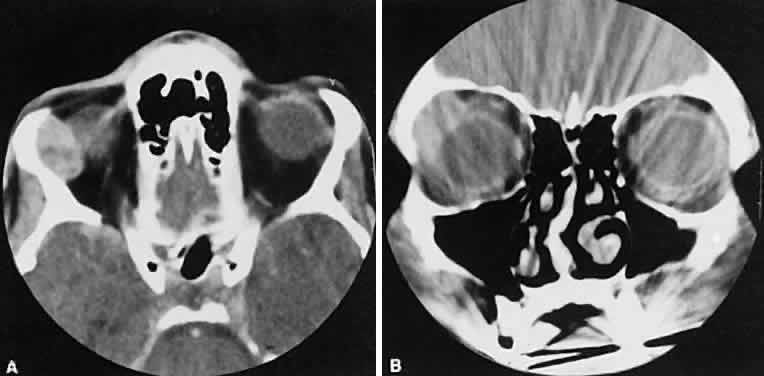

Optimal visualization of the orbit requires imaging from at least two planes. Axial slices should be oriented parallel to the optic nerve (-10 degreesto the orbitomeatal line) and no thicker than 3 mm. Axial views, because of volume averaging, may miss lesions located along the floor or roof. Additional views, typically coronal, can be obtained by reformatting data obtained during axial imaging or by direct coronal scanning.

Direct coronal views usually are preferable because of better resolution.6,7 They can be obtained by having patients lie either prone or supine, extending their neck, and angulating the gantry sufficiently to provide coronal imaging while avoiding artifacts from the teeth. Direct coronal scans also should be no thicker than 3 mm.

Coronal views may need to be reformatted from axial scans if a patient has extensive dental fillings, is anesthetized, or cannot extend the neck sufficiently for direct coronal scanning. The resolution on these images can be improved if data are collected from 1.5-mm contiguous axial slides.6 Spiral CT has resulted in improved multiplanar reformation with thin section (1 to 1.5 mm) axial images. High-resolution images necessary for leukocoria or foreign body imaging are obtained with 1-mm axial slices at 1:1 pitch at 1-mm intervals. Ideally, most screening orbit studies are performed at 3-mm direct axial and direct coronal images.

An appreciation for the various pathologic processes that affect the orbit is facilitated by an understanding of the normal orbital anatomy (Fig. 1). The orbit is a pyramid-shaped bony structure bounded inferiorly by the maxillary sinus, medially by the ethmoidal sinus, and superiorly by the frontal sinus. The sphenoidal sinus is situated posteriorly along the medial orbital wall and has a common wall with the optic canal. The lacrimal gland lies within its fossa located in the superior temporal aspect of the orbit and can be seen on both axial and coronal views.

The extraocular muscles (EOMs), with the exception of the inferior oblique, originate from the anulus of Zinn in the orbital apex. The inferior oblique takes its origin from the frontal process of the maxilla and is seen occasionally on CT imaging. The superior oblique, after originating from the anulus, courses along the superior nasal orbital wall just above the medial rectus muscle before passing through the trochlea. The rectus muscles conveniently form a muscle cone, which is sometimes helpful in terms of differential diagnosis. Before thinner axial slices and multiplanar imaging were available, an enlarged inferior rectus muscle often was imaged as an apical mass, especially if dysthy-roid optic neuropathy was present. The importance of imaging from two different planes cannot be overemphasized in this situation.